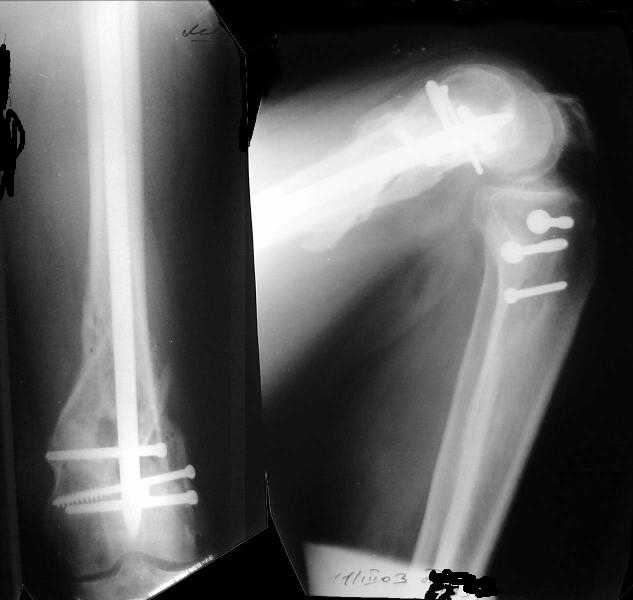

Отправитель: Alexander Chelnokov 28 Декабрь 2003, 21:01

1

2

Exactly. It seems the option looks underestimated.

No, i haven't seen such comparisons. However some advantages of closed antegrade nailing vs conventional plating looks self-evident like no site opeining, no bone skeletization, less blood loss, no need for autografting... If you or other colleagues can help me with the references it would be greatly appreciated. I would be interested also to compare ante- vs retrograde nailing for the localization.

I attached an example of C2 fracture with result of the same technique in 5 months.